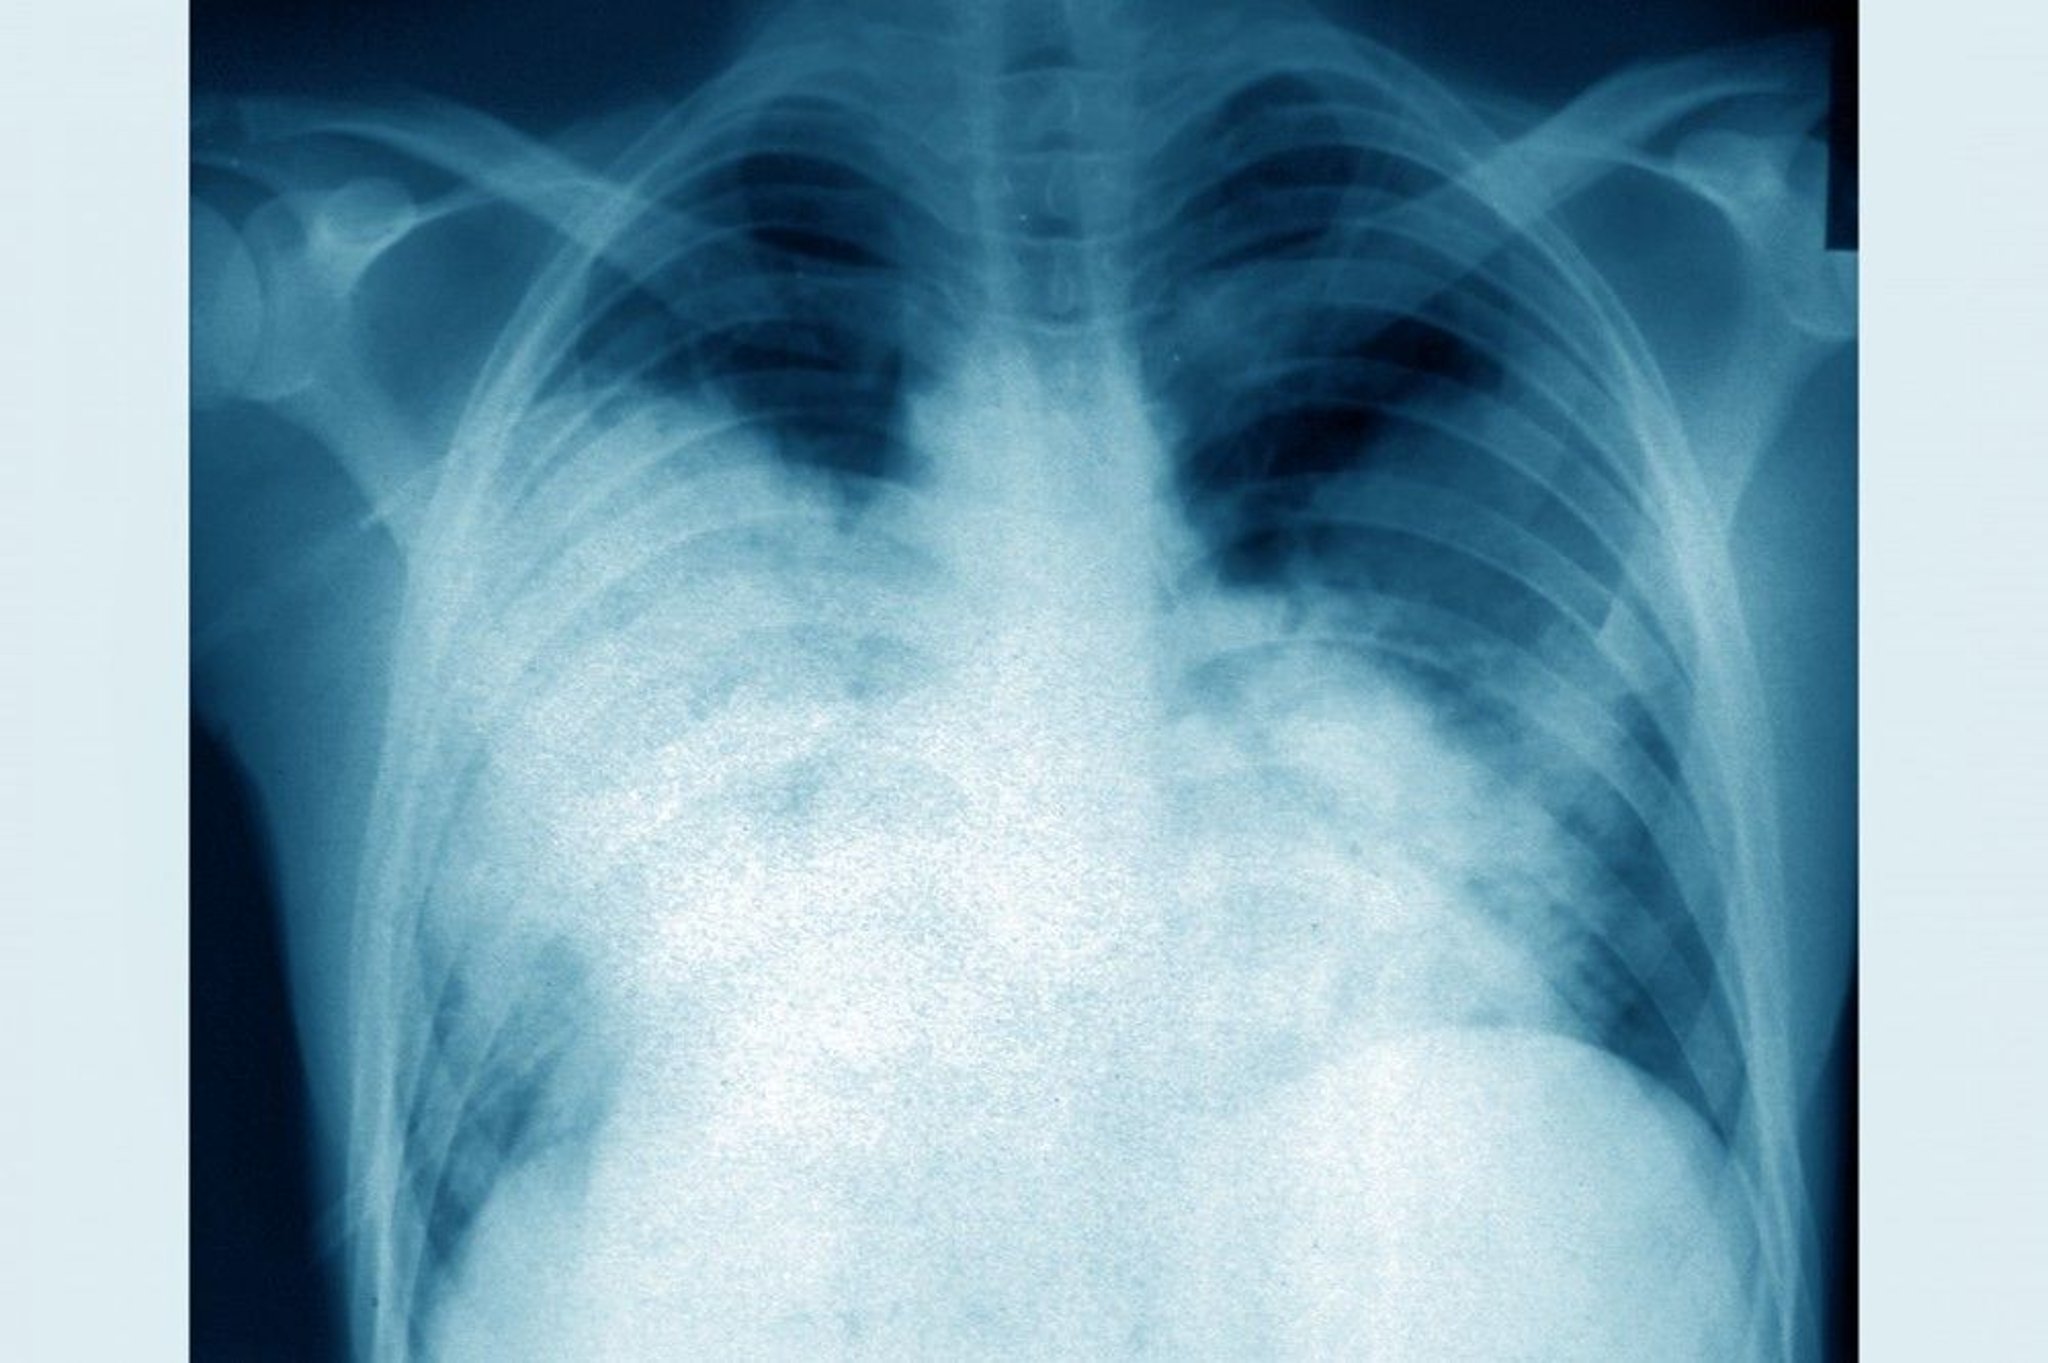

Legionnaire's Disease (Chest Radiograph)

This frontal chest radiograph shows acute bilateral pneumonia (legionnaires' disease caused by Legionella pneumophila).